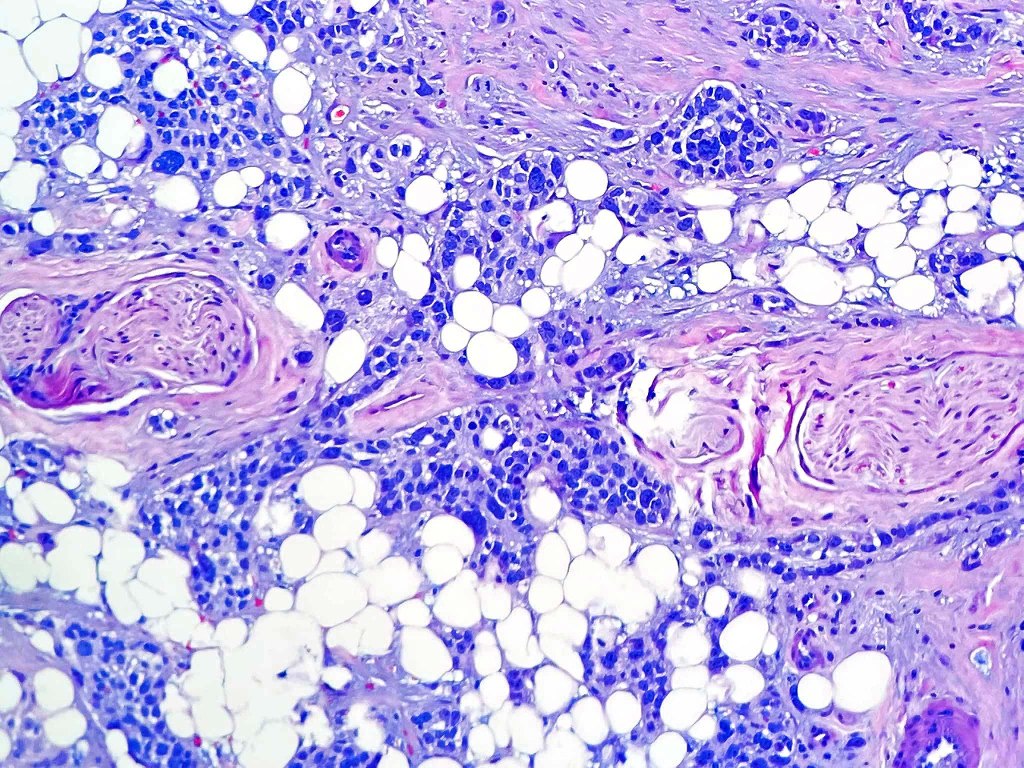

Histological features

•Varying degrees of squamous differentiation- well, moderate, poorly, undifferentiated & anaplastic

•Precursor lesion –actinic keratosis, PUVA keratosis & Bowen disease

•Generally, an infiltrative lower border but exceptionally, may be pushing

. Presence of desmosomes, individual cell keratinization, keratin pearls, keratocysts

•Variable pleomorphism

•Nucleolar prominence

•Mitoses typically numerous & may be atypical

•Variable perineural infiltration & lymphovascular invasion